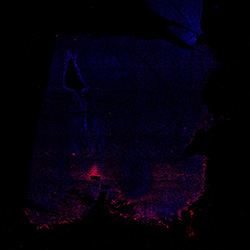

11PCW

DAPI

11PCW human midbrain

MAP2

SOX2

Merged